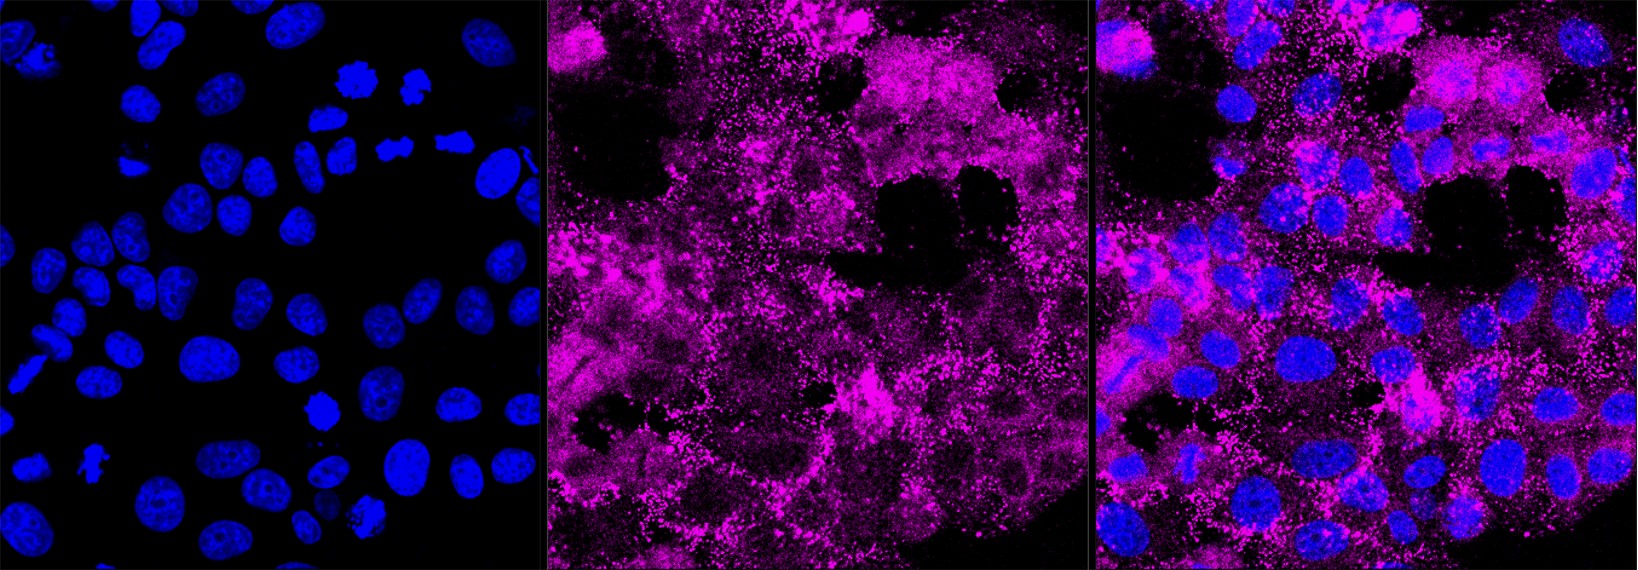

Immunocytochemical staining of HepG2 cells with Histone deacetylase 6 antibody. Nuclei were stained blue with DAPI; Histone deacetylase 6 was stained magenta with Alexa Fluor? 647. Images were taken using Leica stellaris 5. Protein abundance based on laser Intensity and smart gain: Medium. Scale bar, 20 μm.